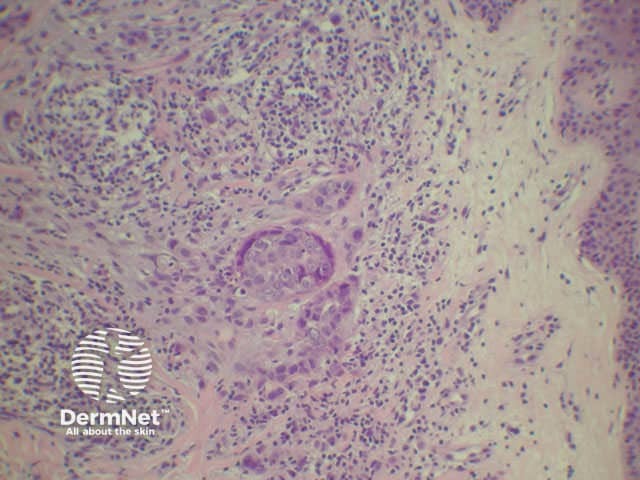

A skin biopsy of the nodule should be performed.

Histologically most tumours are adenocarcinoma and the likely origin may be suggested by histochemical stains on the biopsy and tumour markers such as CEA.